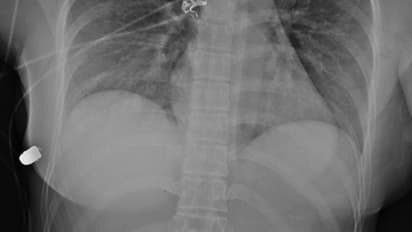

വാരിയെല്ലുകള്ക്ക് പരിക്ക് പറ്റിയെങ്കിലും ഹൃദയം, ശ്വാസകോശം തുടങ്ങിയ സുപ്രധാനമായ ആന്തരീകാവയവങ്ങള്ക്ക് യാതൊരു കേടുപാടും സംഭവിച്ചില്ല. അത്യപൂര്വ്വമായ സംഭവമെന്ന നിലയ്ക്ക് ഈ സംഭവം പഠനവിധേയമാക്കുകയായിരുന്നു വിദഗ്ധര്. യുവതിയുടെ സ്കാനിംഗ് റിപ്പോര്ട്ടും മുറിവുകളുടെ ഫോട്ടോഗ്രാഫുമെല്ലാം പുറത്തുവന്നിട്ടുണ്ട്.